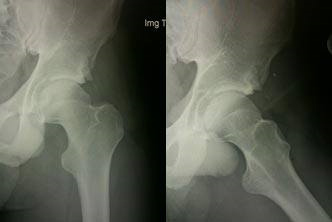

Twenty-two year-old soccer player with progressive hip pain over the past 2 years. The patient originally injured his hip playing during a free-kick and has tried conservative management including physical therapy, anti-inflammatories, and rest. Radiographs demonstrated a large well-corticated bony prominence adjacent to the anterolateral acetabulum labrum extending towards the anterior inferior iliac spine. MRI scan showed a tear of the anterolateral labrum. The patient underwent an arthroscopic resection of the bony impingement lesion as well as fixation of the labrum. He remains pain-free and has had no hip residual pain.

Prior to Resection of the Impingement Lesion

After Arthroscopic Impingement Resection